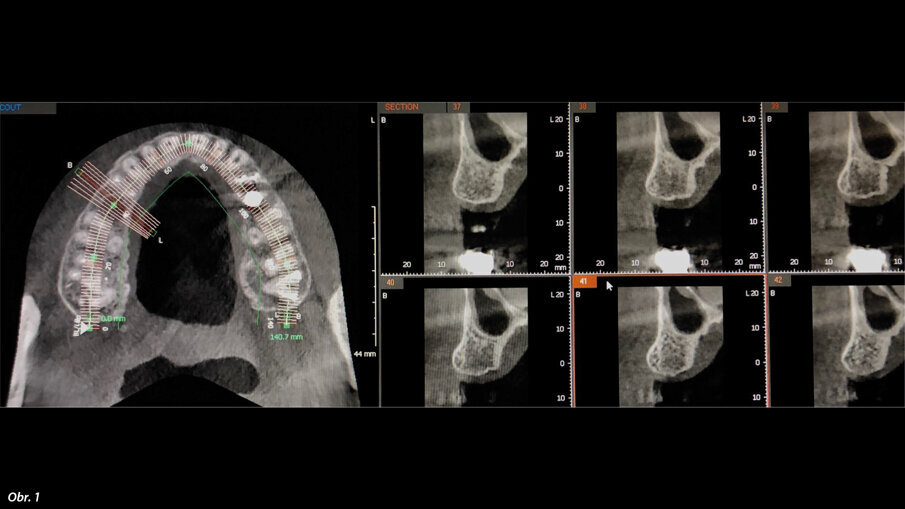

Dále byl použit Er:YAG laser s vlnovou délkou 2940 nm (LightWalker AT) opatřený digitálně kontrolovaným násadcem (X-Runner, Fotona) (obr. 4). Laser byl použit za parametrů 380 mJ a 20 Hz, působících v superkrátkých pulzech (50 mikrosekund). Byl použit externí zdroj sterilního fyziologického roztoku skladovaného při 5 °C v chladničce a tento roztok byl přiváděn pomocí peristaltické pumpy kvůli podpoře fototermické ablace a snížení teploty v místě zákroku. Digitálně kontrolovaný násadec umožňuje naprogramování a přesné provedení kruhové osteotomie o průměru 3,5 mm, tedy stejného průměru jako je poslední vrták dodávaný výrobcem implantátu. Během osteotomie byla pomocí milimetrové sondy kontrolována hloubka zavádění, až do dosažení předem nastavené hloubky 12 mm. Autor raději zavádí implantáty subkrestálně o 2 mm hlouběji, aby se předešlo resorpci v důsledku náklonu osy implantátu a bylo možno mít větší kontrolu nad emergence profilem náhrady. Byl zaveden kónický šroubový implantát vyrobený z titanu IV. třídy s opískovaným a kyselinou naleptaným povrchem (HELI, IDC). Implantát měl největší průměr 4,2 mm u vnějšího závitu a délku 10,0 mm. Po zavedení byl pomocí násadce Osstell (obr. 5, 6) určen kvocient stability implantátu (ISQ). Lalok byl sešit (obr. 7), byl pořízen RTG snímek (obr. 8) a stehy byly odstraněny po pěti dnech. V té době byl pacient požádán, aby zhodnotil pooperační bolest, kterou pociťoval, a to formou sdělení přiřazené číselné hodnoty od 0 do 10.

Stabilizovaný laser preparující osteotomii, pracoval při 380 mJ, 20 Hz a 50 mikrosekundách